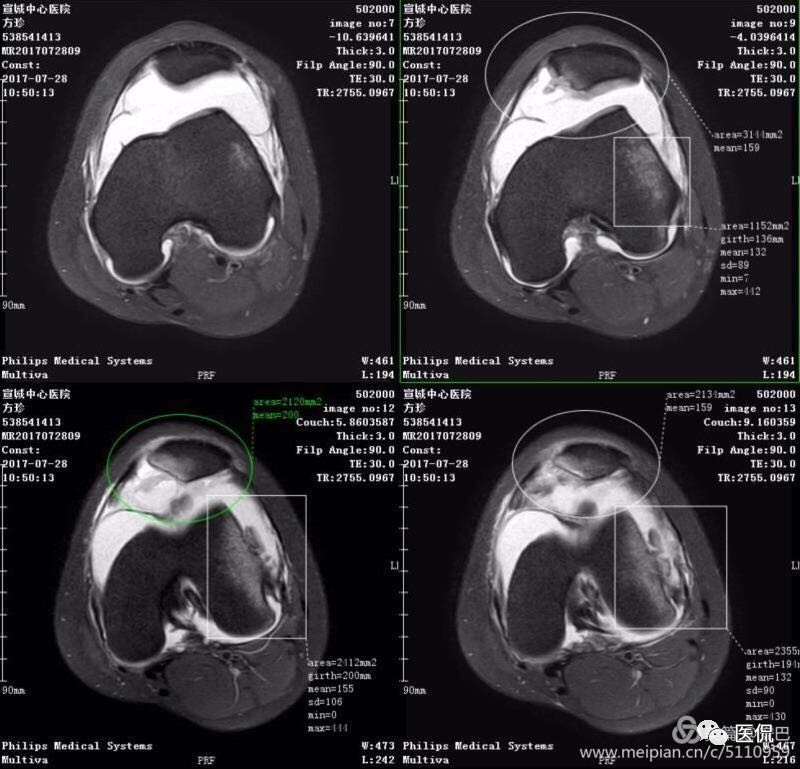

MR表现

1、单液-液平面:上层呈短T1、长T2信号、T2压脂像低信号、Pd像呈高信号;下层呈中等T1、T2信号、T2压脂像和Pd像呈较高信号。

2、双夜-液平面:上层呈短T1、长T2高信号、T2压脂像低信号、Pd像呈高信号;中层呈长T1、长T2信号、T2压脂像和Pd像呈较高信号;下层呈中等T1、T2信号、T2压脂像和Pd像呈较高信号。

3、多液-液平面:最上层呈无信号区;上层呈短T1、长T2高信号、T2压脂像低信号、Pd像呈高信号;中层呈长T1、长T2信号、T2压脂像和Pd像呈较高信号;下层呈中等T1、T2信号、T2压脂像和Pd像呈较高信号。